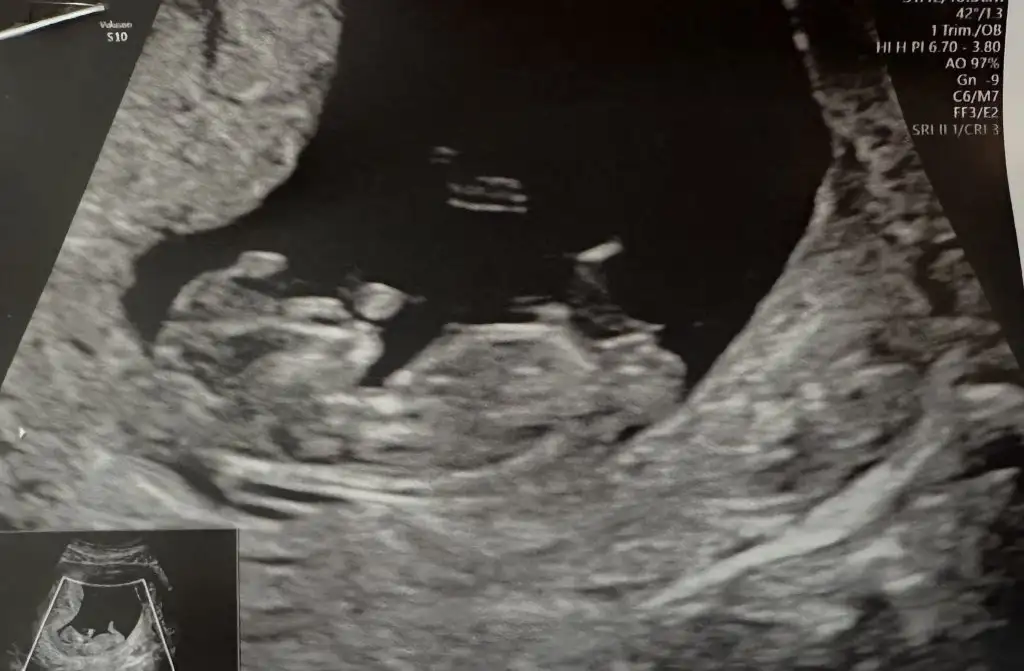

Kese : 6+3

Kalp: 6+3